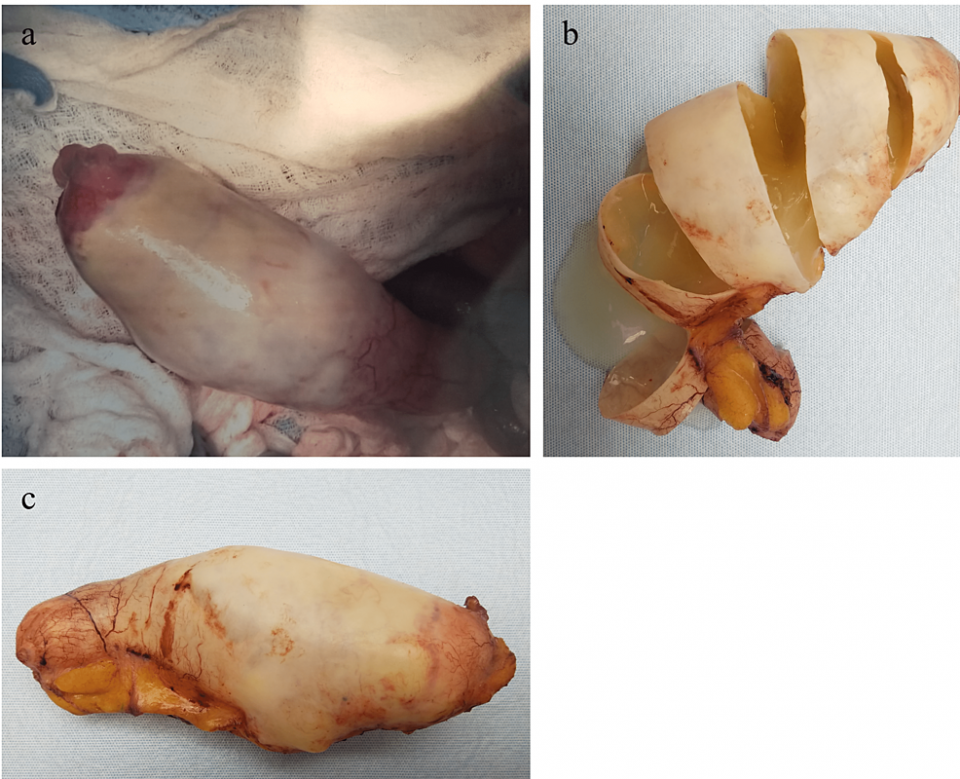

A 59-year-old male presented with microscopic hematuria. Renal ultrasound showed a large tubular lesion in the pelvis. CT abdomen and pelvis with IV and oral contrast demonstrated a 14.5 cm x 6.3 cm x 5.6 cm peripherally calcified tubular fluid attenuation lesion in the right hemipelvis. Though surgery was recommended for management, the patient declined surgery and wished to be managed non-operatively. The patient’s request was followed, and the patient was counseled that if the findings did not normalize on follow-up imaging after non-operative management, then surgery would be highly recommended. A follow-up CT scan with IV contrast five months later re-demonstrated the RLQ tubular cystic mass measuring 14.4 cm x 5.3 cm in the coronal plane with heterogeneous mural calcifications lying adjacent to the appendiceal tip. An open appendectomy was performed and the cystic appendiceal mass was removed (Figure 1). Because pathological examination demonstrated an LAMN confined to the appendix with an intact serosa and proximal and mesenteric bowel margins negative for neoplasms, staged as pTis, appendectomy alone was considered suitable for treatment.

To reduce risks of rupture and PMP progression and examine for the presence of LAMN pathologically, surgical removal of the appendix is crucial for further diagnosis and management [1-3]. Options for removal include open and laparoscopic resection. While open surgery is sometimes recommended to prevent LAMN rupture and PMP, there are documented cases of rupture and PMP in both open and laparoscopic resection with no comparative study available [5]. Including a cuff of the cecum without involving the ileocecal valve is preferred during appendectomy to ensure removal of the lesion [6]. Gross examination shows a cystically dilated mucinous appendix with a hyalinized, thin, fibrotic, or calcified wall and a smooth, corrugated, or granular lining (Figure 1) [1-2]. Because LAMN does not spread via the hematogenous or lymphatic route, an appendectomy is generally acceptable for the management of LAMN confined to the appendix on pathology, with conservative follow-up and surveillance if the appendectomy margins involve acellular mucin or neoplastic epithelium (Figure 5) [2, 7-8]. If acellular mucin is extruded on the appendiceal serosal surface without peritoneal dissemination, an appendectomy with close observation and evaluation for PMP via routine imaging appears to be sufficient [1-2]. Though recommendations on imaging frequency and duration may vary given there are no formal guidelines, we recommend annual CT imaging for five to ten years. Additionally, supplemental right hemicolectomy does not provide advantages over appendectomy in these patients and can involve the retroperitoneum, which may result in the seeding of the mucinous epithelium [2, 8]. If there is peritoneal dissemination, management may require appendectomy, irrigation, a biopsy of peritoneal nodules, peritonectomy, and chemotherapy [3].